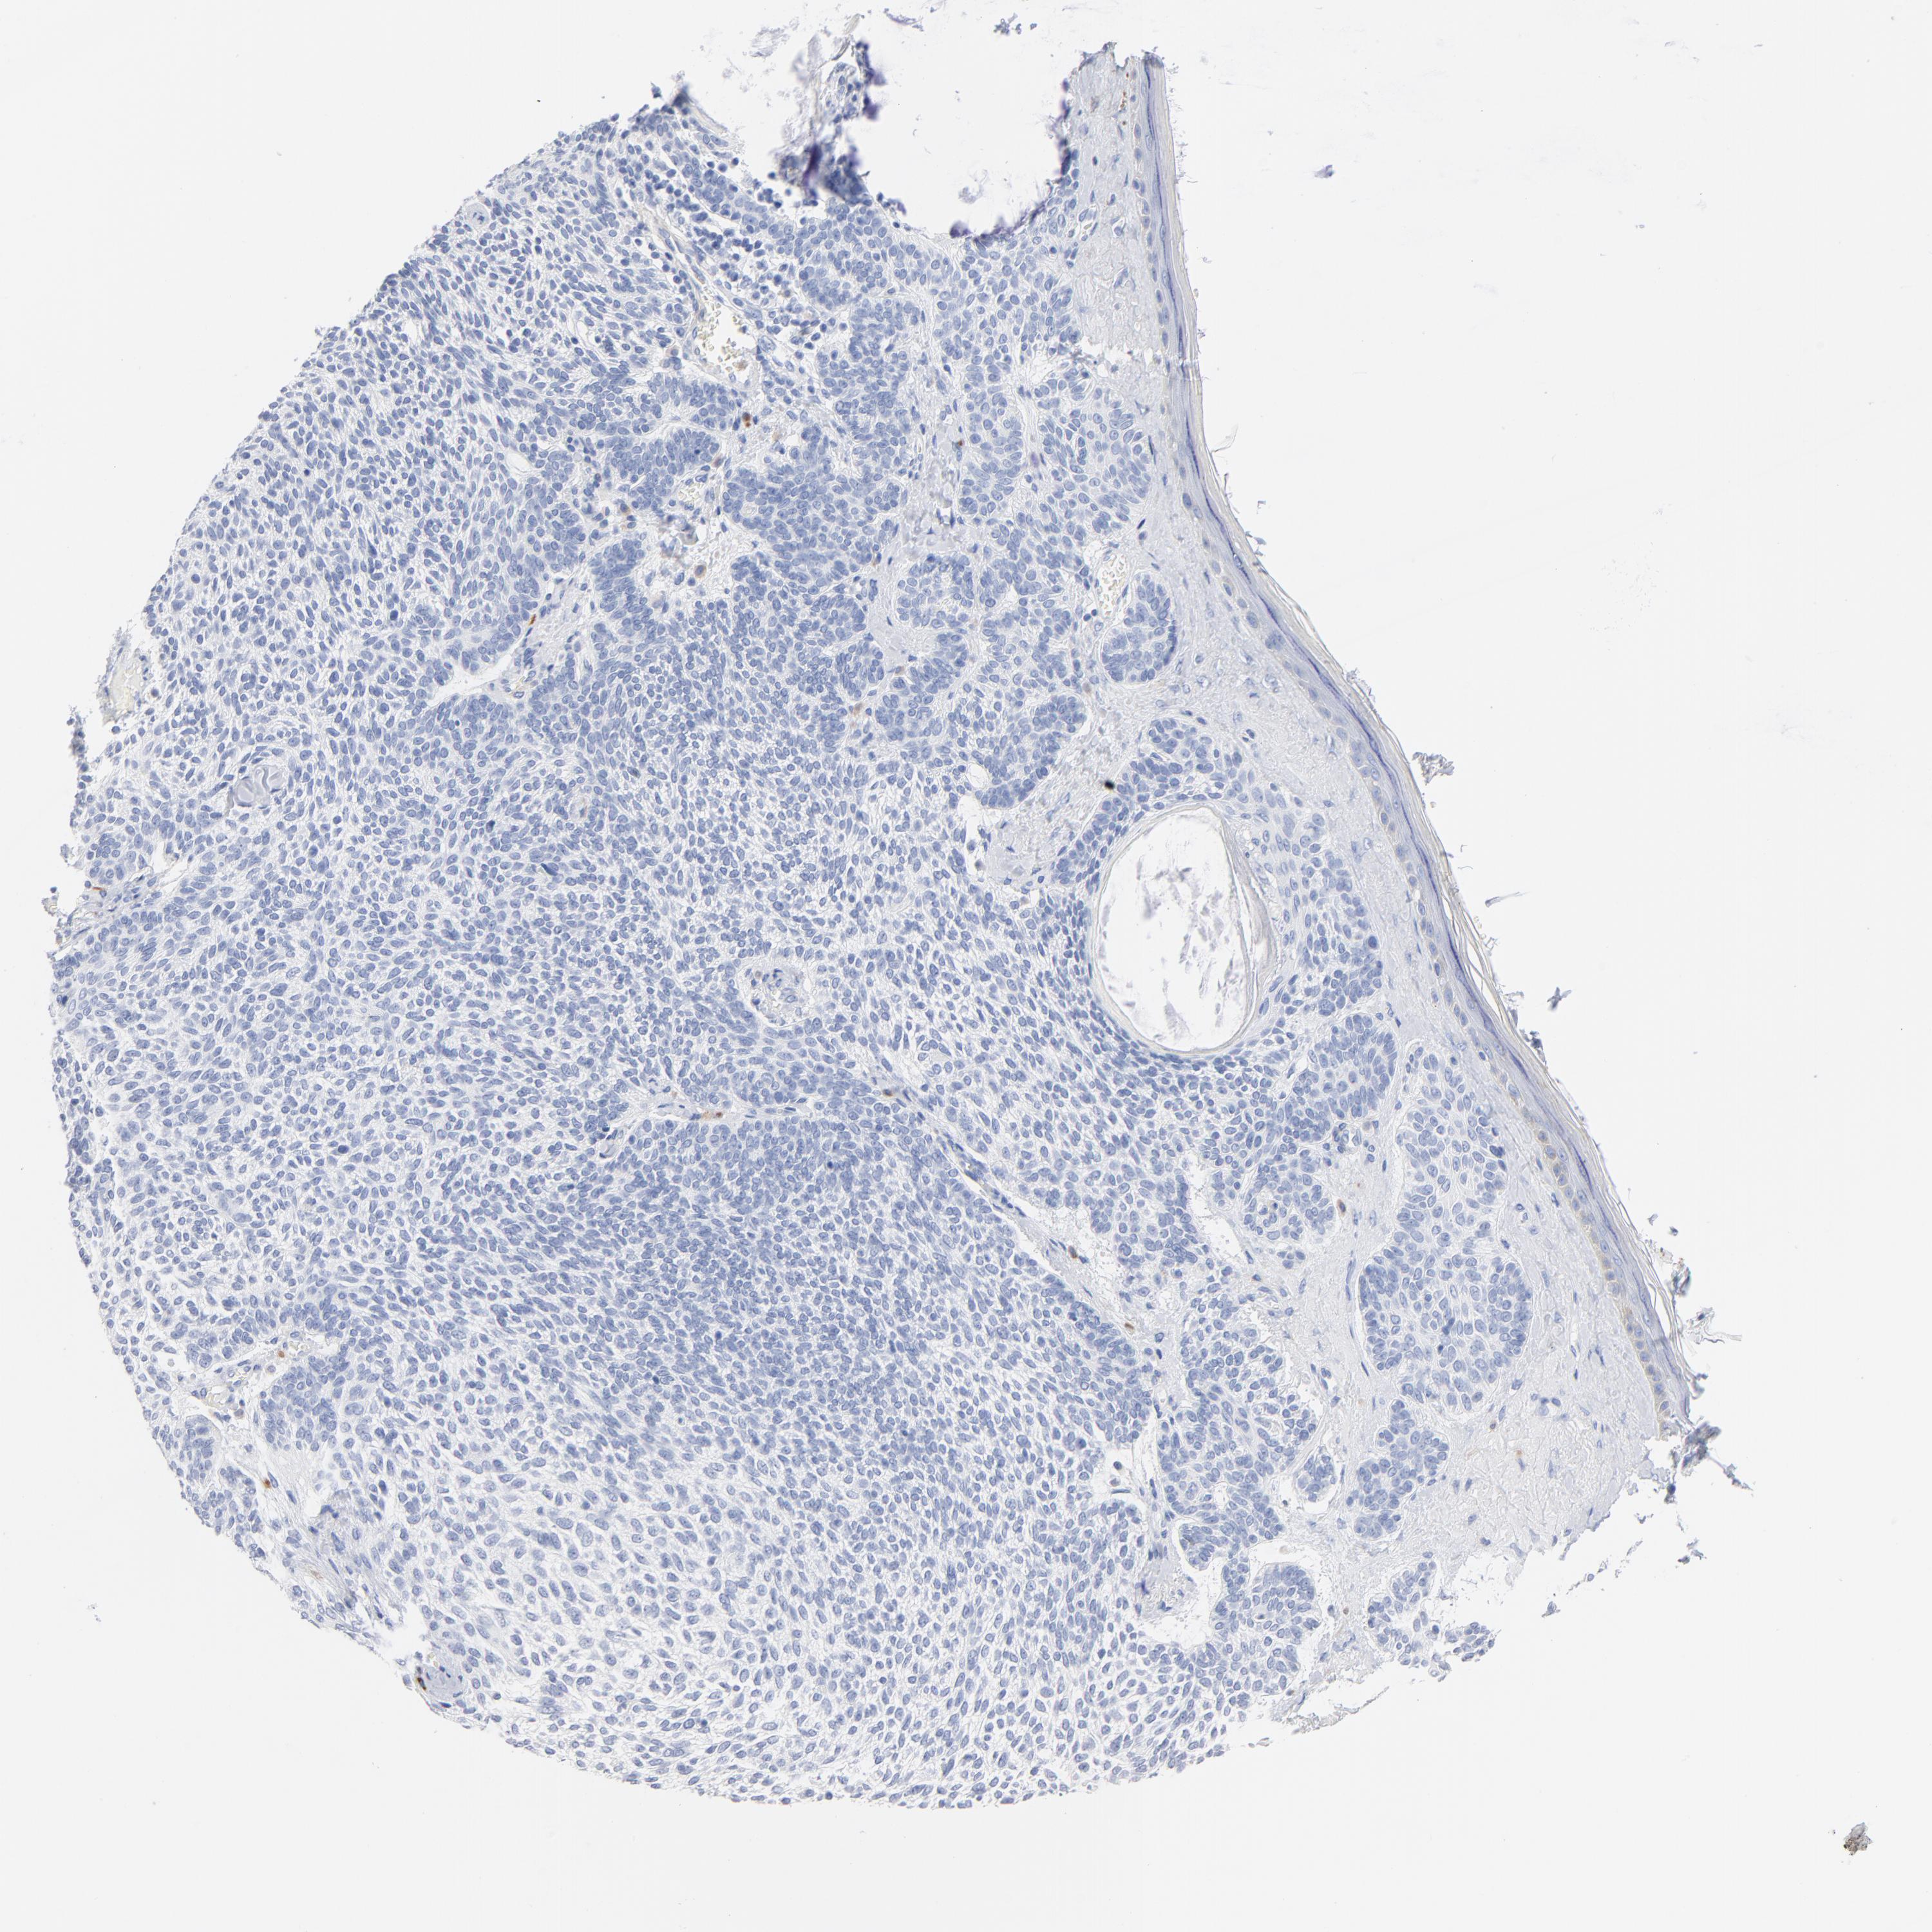

Basal cell and squamous cell cancer

SKIN CANCER - Protein expressioni

A mouse-over function shows sample information and annotation data. Click on an image to view it in a full screen mode. Samples can be filtered based on level of antibody staining by selecting one or several of the following categories: high, medium, low and not detected. The assay and annotation is described here.

Antibody stainingi

Antibody staining in the annotated cell types in the current human tissue is reported as not detected, low, medium, or high, based on conventional immunohistochemistry profiling in selected tissues. This score is based on the combination of the staining intensity and fraction of stained cells.

Each image is clickable and will lead to virtual microscopy that enables deeper exploration of all samples and also displays staining intensity scores, fraction scores and subcellular localization as well as patient and tissue information for each sample.

Antibody HPA003596

Staining

High

Medium

Low

Not detected

Intensity

Strong

Moderate

Weak

Negative

Quantity

>75%

75%-25%

<25%

None

Location

Nuclear

Cytoplasmic/membranous

Cytoplasmic/membranous,nuclear

Squamous cell carcinoma, NOS

Basal cell carcinoma